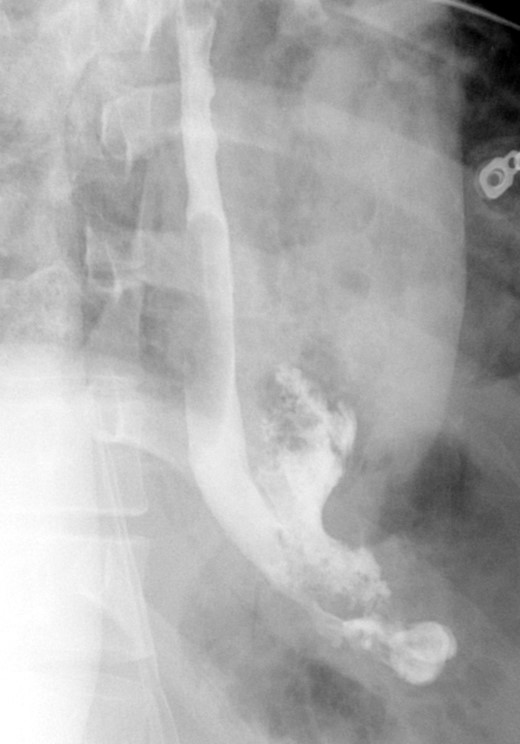

A computed tomographic scan revealed air and fluid surrounding the esophagus (Fig. 1). Esophagogram performed with water-soluble contrast media showed a distal esophageal perforation with a free leak into a large mediastinal cavity to the left of the esophagus (Fig. 2). The patient was triaged directly to the operation room. A left chest tube was placed with improvement in his oxygenation, and grossly murky fluid was drained. Esophagogastroduodenoscopy (EGD) was performed next and revealed a very small caliber esophagus with concentric ringed appearance. A tight stricture was noted in the mid-esophagus, which only allowed passage of a pediatric gastroscope. In the lower esophagus, a 2-cm tear with necrotic edges was visualized 3 cm above the gastroesophageal (GE) junction. With this diffusely strictured and very diseased appearance of the esophagus, the decision was made to proceed with stent placement and thoracoscopic drainage of the mediastinum rather than primary surgical repair via thoracotomy. A fully covered, 15 cm × 19 mm, EndoMAXX® esophageal stent was successfully placed covering the perforation site. Mediastinal washout and drainage was performed subsequently via left thoracoscopy. A postoperative esophagram showed no leak and the patient was started on a liquid diet that was tolerated well. His hospital stay was uneventful, and he was discharged on twice daily high-dose proton pump inhibitor (PPI) on post-operative Day 5. He was placed on a mechanical soft diet on discharge. Repeat upper GI study with water soluble contrast postoperatively showed no evidence extravasation. (Fig. 3)

Shows metallic expandable stent in a satisfactory position in the mid to lower thoracic esophagus extending to the GE junction. Water-soluble contrast is seen filling the stent with no evidence of extravasation.